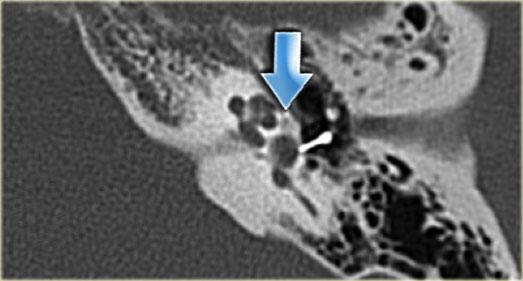

Cống tiền đình giãn rộng hai bên (mũi tên đen). Trụ ốc tai xương không quan sát thấy (mũi tên trắng).

Cống tiền đình giãn rộng

Cống tiền đình là một ống xương hẹp (cống) nối túi nội dịch với tai trong (tiền đình).

Chạy qua ống xương này là một ống gọi là ống nội dịch.

Cống tiền đình giãn rộng có liên quan đến tình trạng nghe kém tiếp âm tiến triển.

Sự tiến triển này được cho là có liên quan đến chấn thương đầu nhẹ, làm tai trong tiếp xúc với sóng áp lực qua cống tiền đình giãn rộng.

Cống tiền đình giãn rộng có liên quan đến sự vắng mặt của trụ ốc tai xương ở hơn 90% bệnh nhân.

Bên trái là hình ảnh của một bệnh nhân có cống tiền đình giãn rộng hai bên.

Lưu ý rằng trụ ốc tai xương không quan sát thấy.